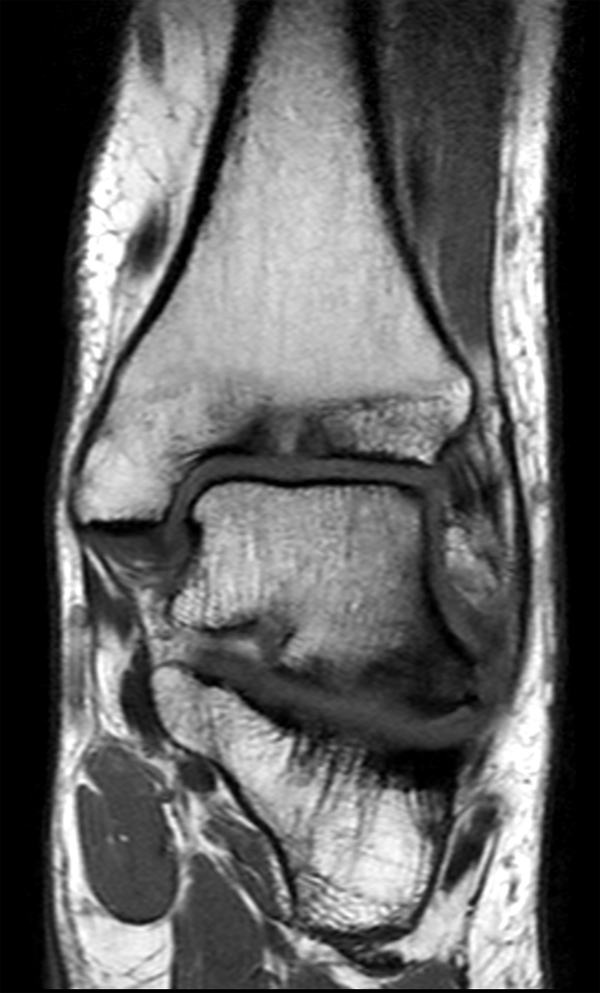

Coronal PDw TSE